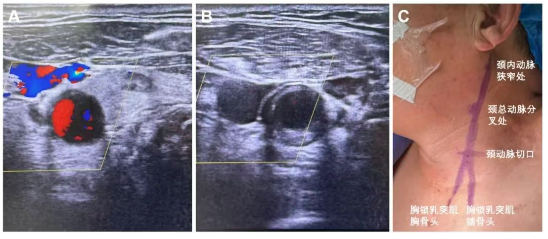

全麻后颈动脉超声标记颈总动脉切口位置、颈总动脉分叉、颈内动脉C1病变位置,确认手术切口至颈总动脉分叉距离大于5cm,颈总动脉直径大于6mm,颈内动脉直径大于4mm。

在锁骨上2-3cm,胸锁乳突肌前缘做一长约3-4cm的横向切口,逐步切开皮肤、皮下及颈阔肌,暴露颈动脉鞘,纵行切开颈动脉鞘显露颈总动脉,分别环绕皮筋,美兰标记颈动脉穿刺点。穿刺颈动脉成功,置入4F动脉鞘。同时穿刺股静脉置入静脉回流鞘管备用。